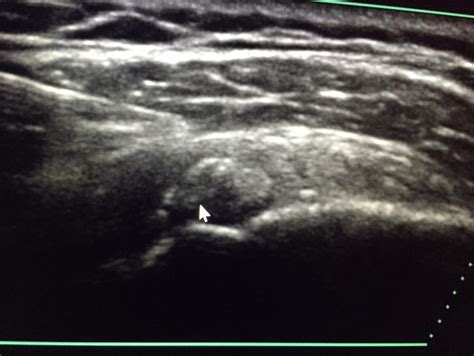

• Ultrasound-guided needle aspiration: A procedure where a needle is inserted into the calcium deposit to remove it, often combined with a corticosteroid injection.